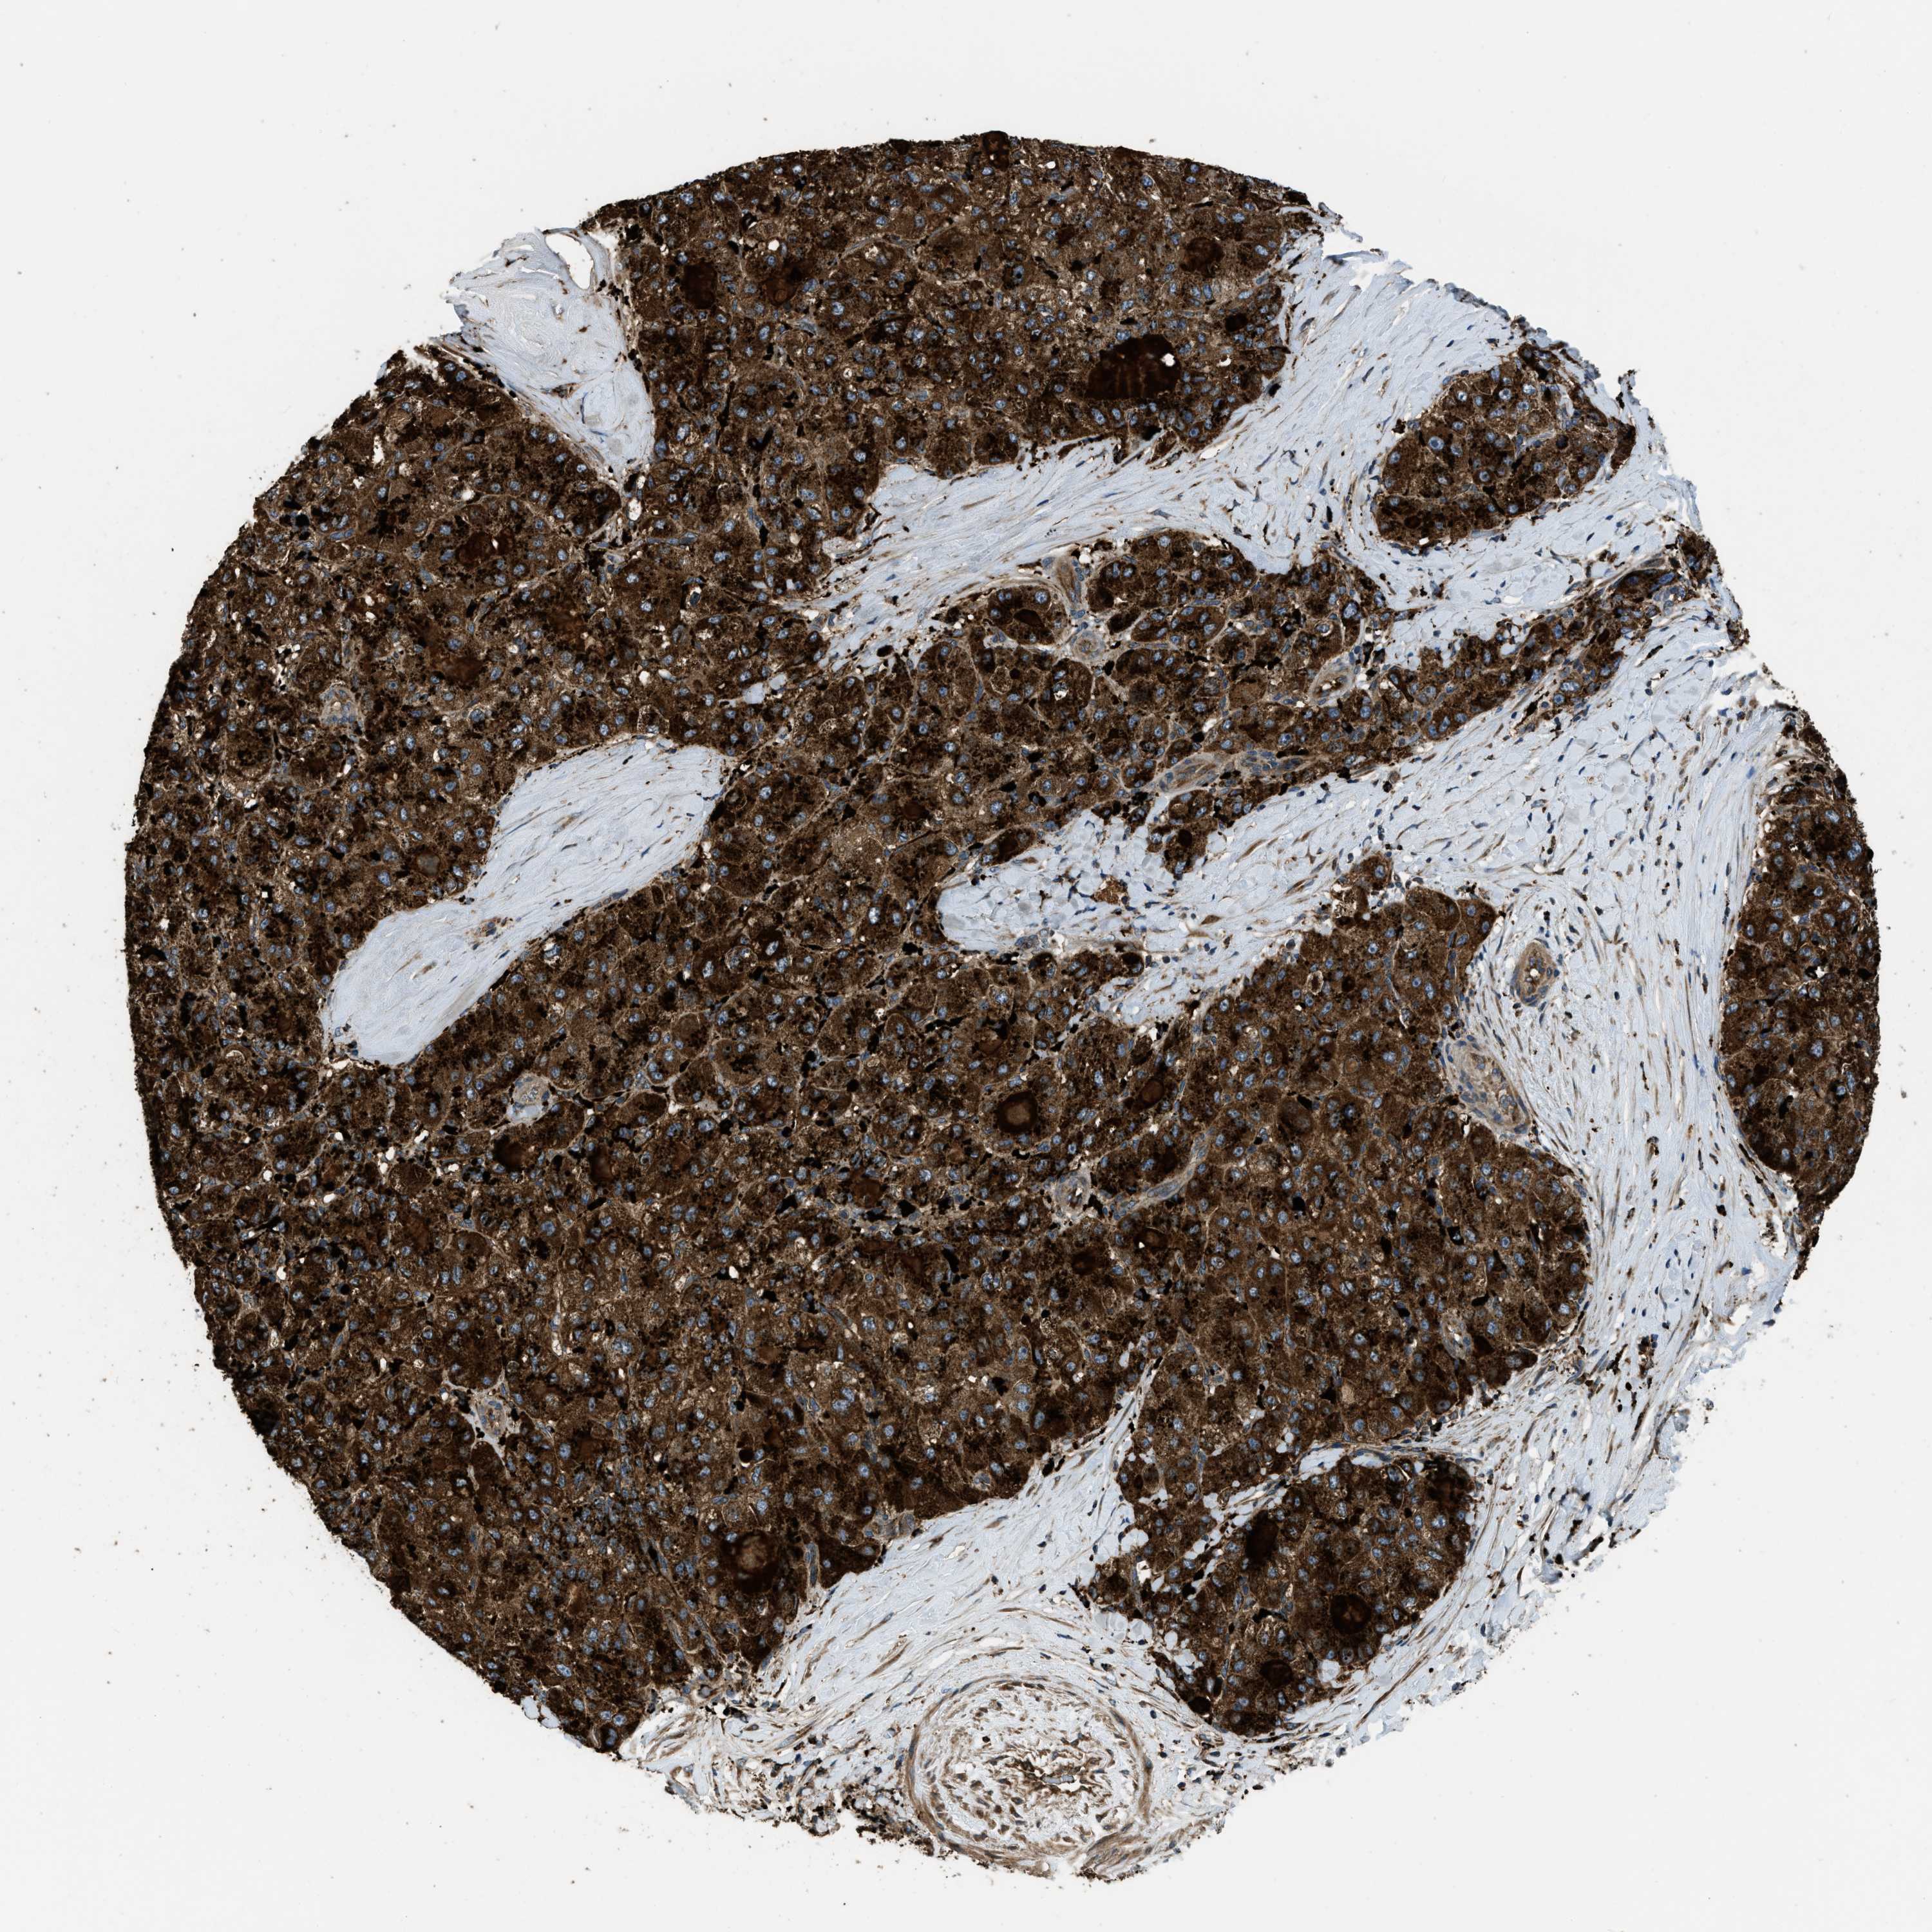

LIVER CANCER - Protein expressioni

A mouse-over function shows sample information and annotation data. Click on an image to view it in a full screen mode. Samples can be filtered based on level of antibody staining by selecting one or several of the following categories: high, medium, low and not detected. The assay and annotation is described here.

Note that samples used for immunohistochemistry by the Human Protein Atlas do not correspond to samples in the TCGA dataset.

Antibody stainingi

Antibody staining in the annotated cell types in the current human tissue is reported as not detected, low, medium, or high, based on conventional immunohistochemistry profiling in selected tissues. This score is based on the combination of the staining intensity and fraction of stained cells.

Each image is clickable and will lead to virtual microscopy that enables deeper exploration of all samples and also displays staining intensity scores, fraction scores and subcellular localization as well as patient and tissue information for each sample.

Antibody HPA025226

Antibody CAB019296

Staining

High

Medium

Low

Not detected

Intensity

Strong

Moderate

Weak

Negative

Quantity

>75%

75%-25%

<25%

None

Location

Nuclear

Cytoplasmic/membranous

Cytoplasmic/membranous,nuclear

Cholangiocarcinoma

Carcinoma, Hepatocellular, NOS